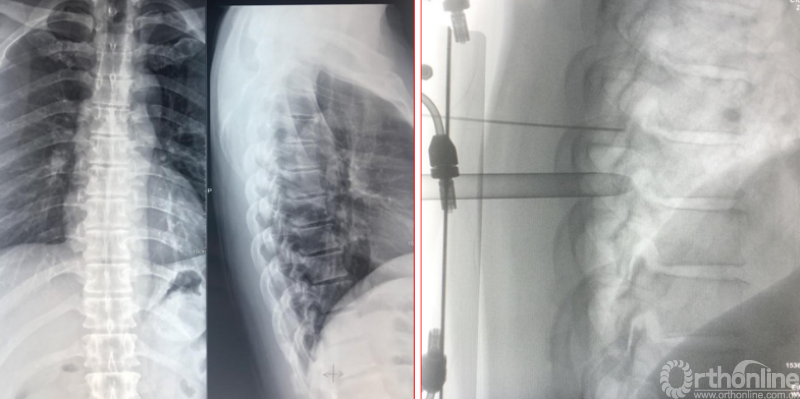

术后第二天资料

术后影像学资料

术后资料